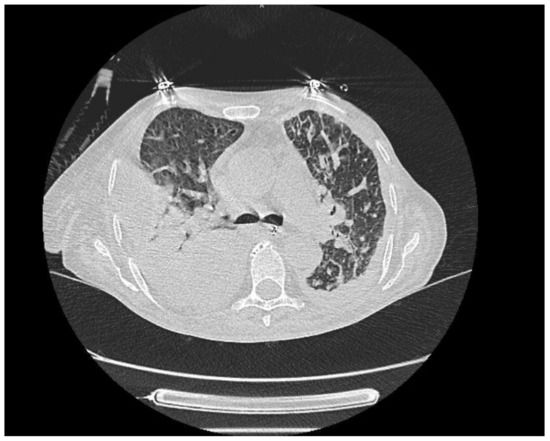

| Patient 6 | Nonspecific | Palbociclib | Bilateral |

| Interstitial Pneumonia (NSIP) | symmetrical | ||

| ground-glass | |||

| opacities, reticular densities, and | |||

| traction | |||

| bronchiectasis. (Figure 3) | |||